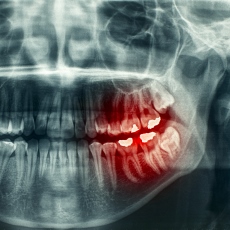

Your dentist will ask about your symptoms, look at your teeth, and probe them with dental instruments. In some cases, you may need dental x-rays.

- Panoramic Dental X-Ray (American College of Radiology; Radiological Society of North America) Also in Spanish

- Impacted tooth - a tooth that did not erupt (break through the gum) when it should have. It is usually wisdom teeth that are impacted, but it can sometimes happen to other teeth.